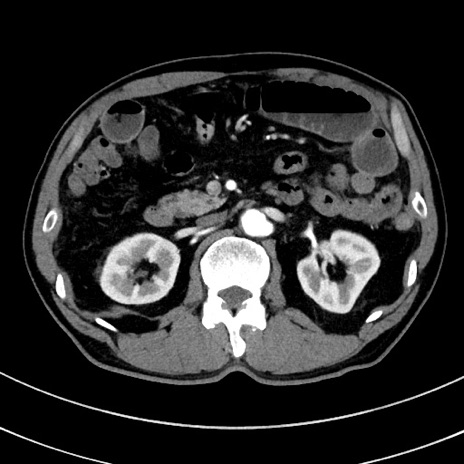

症例8(横断像)

【症例】 60歳代男性

【主訴】 黒色吐物

【現病歴】 4日前から嘔気自覚、2日前の朝食後にも嘔気あり、自分で手で嘔吐反射起こし嘔吐したところ血が混ざっていたため受診。

【既往歴】 5年前汎発性腹膜炎を伴う急性虫垂炎で手術、高血圧、前立腺肥大症、高脂血症

【身体所見】 腹部正中に手術癩痕あり 腹部平坦・軟圧痛なし膨満感あり

【データ】WBC 8400、CRP 4.54